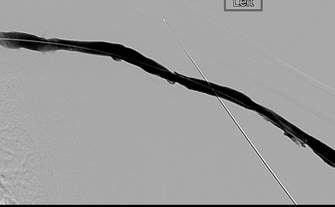

Trombectomía de oclusión de fístula braquiocefálica izquierda

Fistulograma que demuestra la oclusión trombótica de una fístula AV braquiocefálica izquierda (nota: reflujo arterial de contraste).

Tras la primera pasada con el catéter DVX de AngioJet (no se usaron trombolíticos).

Tras la segunda pasada con el catéter DVX y la angioplastia con balón de la estenosis subyacente. Sin impedancia para el flujo de avance en la FAV.

Una vez que se establezca el flujo de avance y se trate la estenosis, los trombos residuales deberían resolverse.